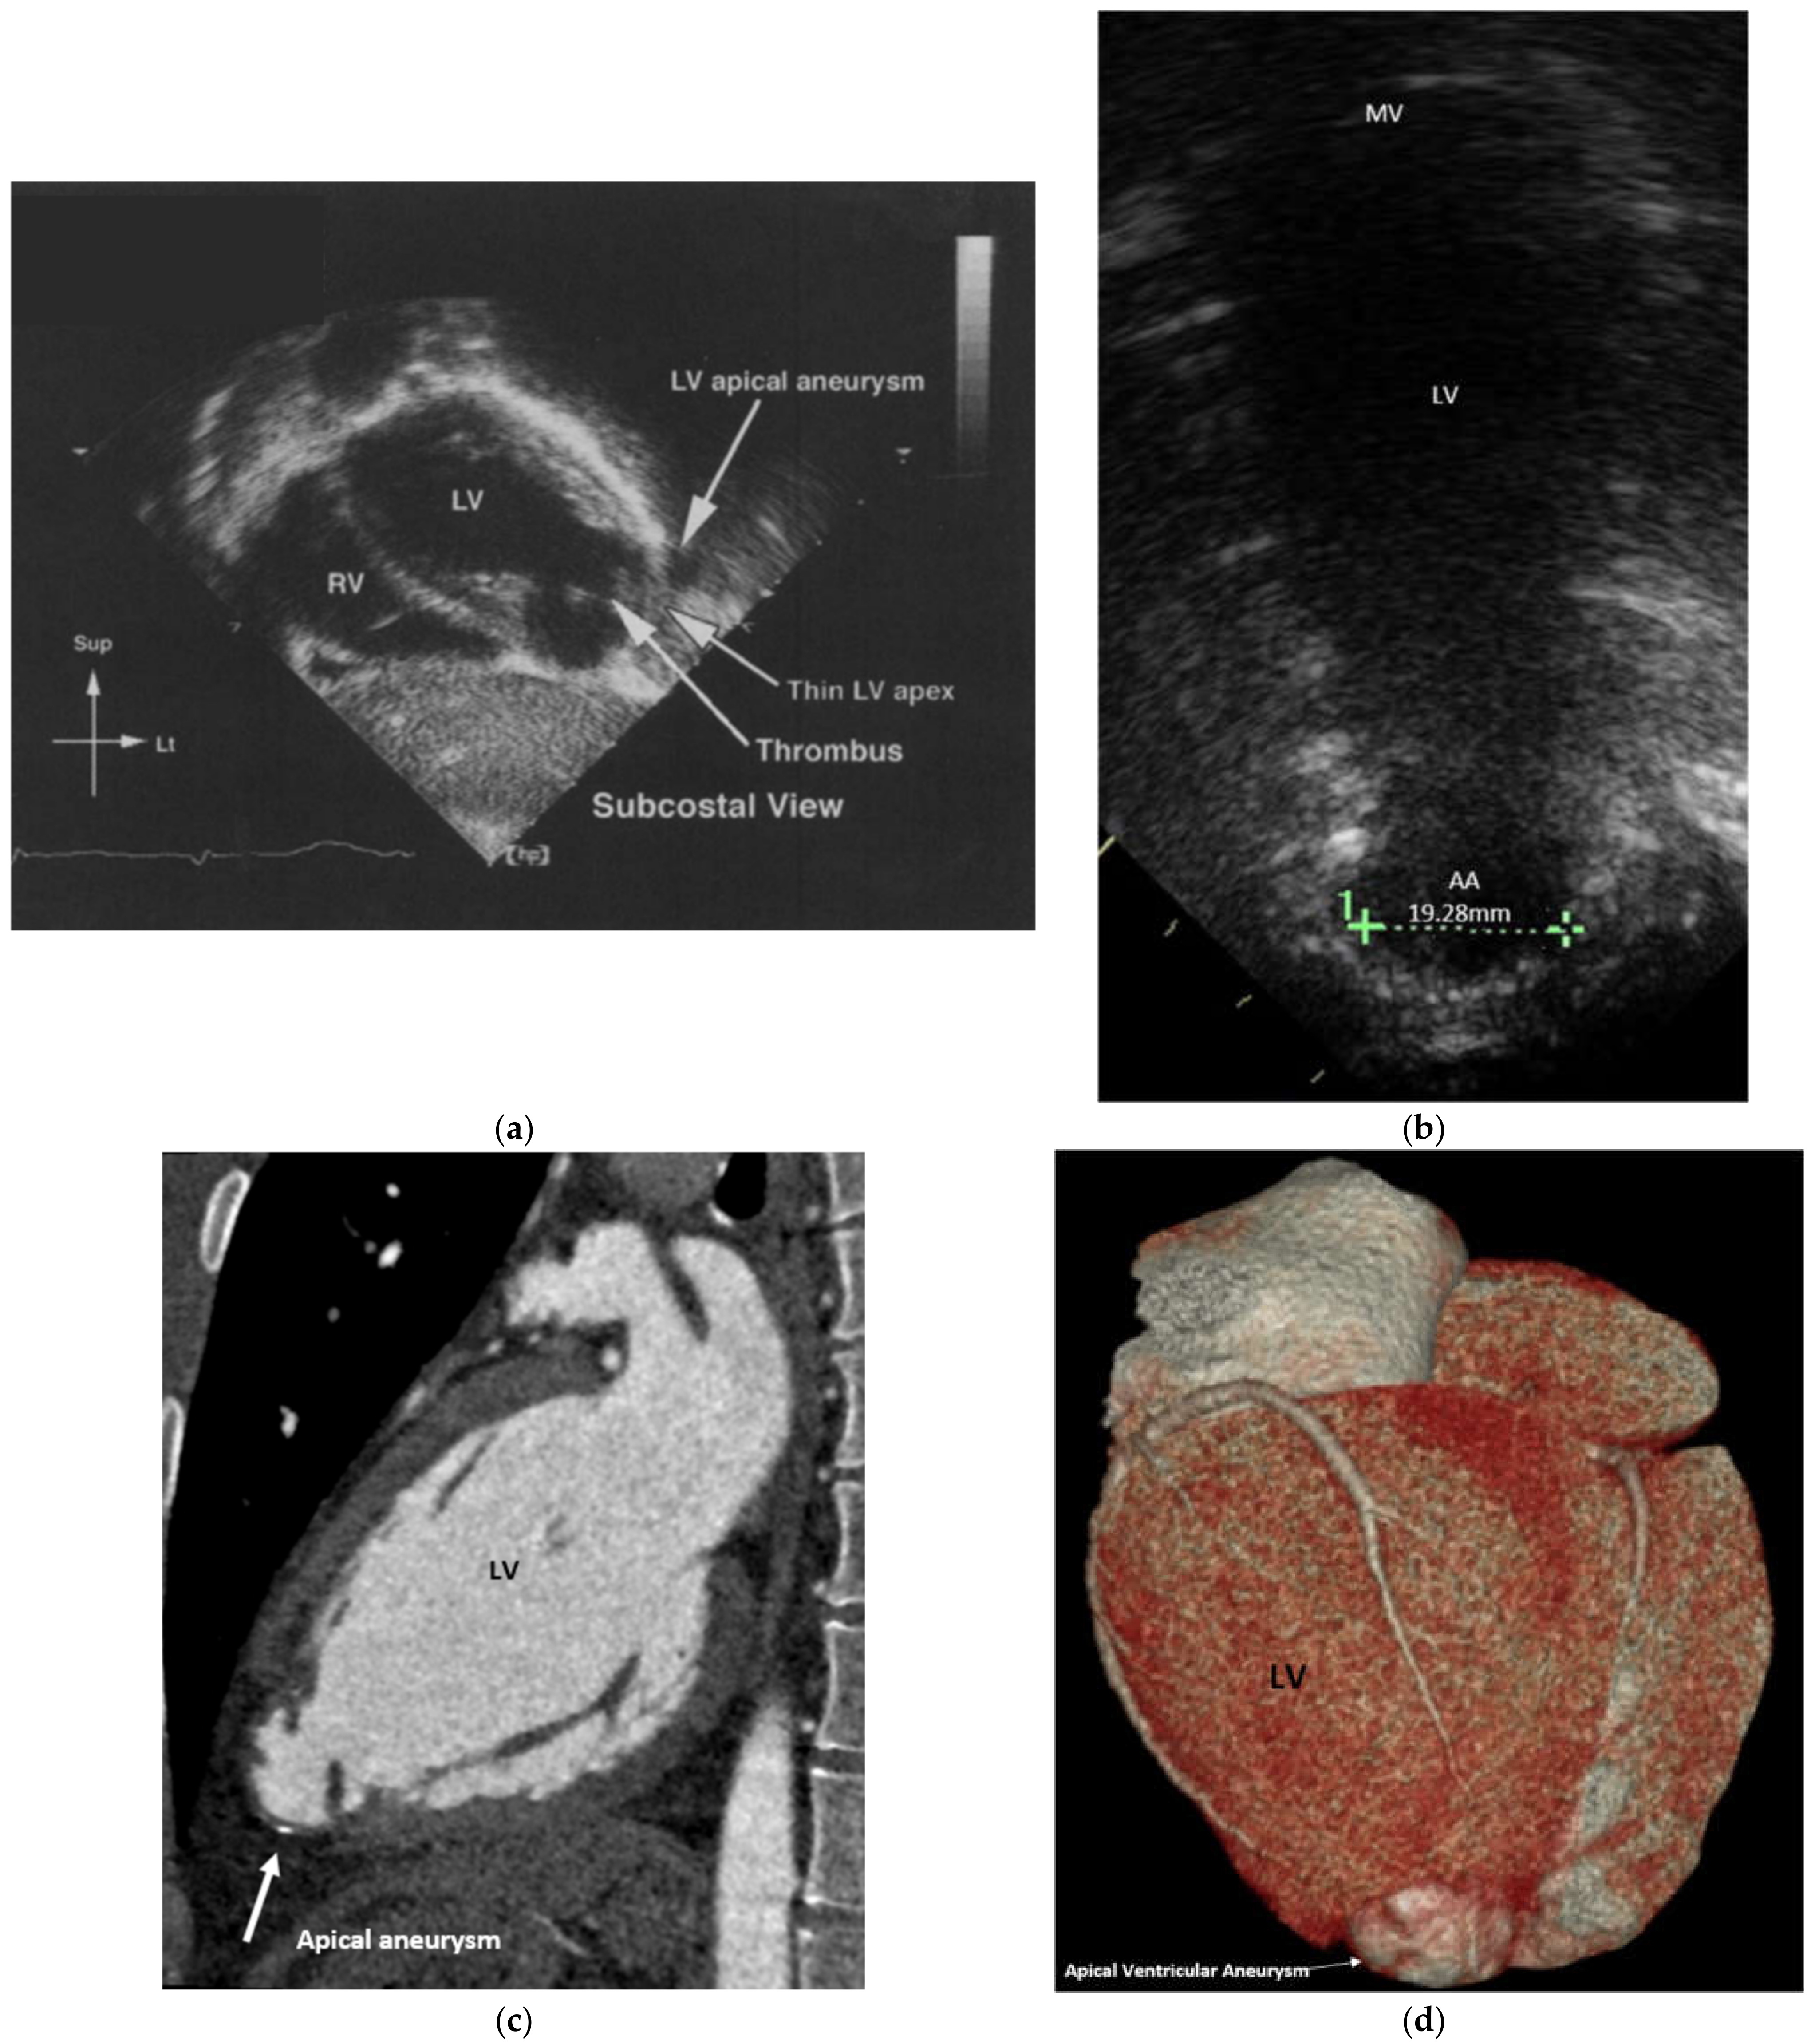

Major Complication Following Kawasaki Disease in an Infant—The Development of Apical Infarction and Aneurysm Formation

2. Case Report